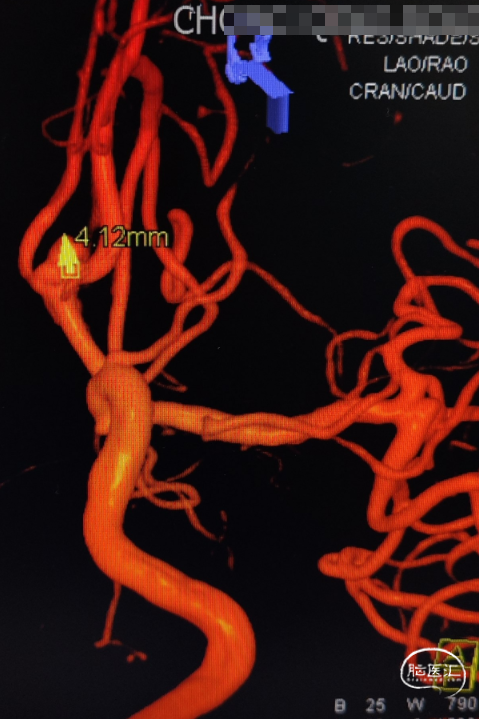

完善头颅CTA显示:前交通动脉瘤、左侧大脑中M1段末端动脉瘤。

DSA造影确认前交通动脉瘤、左侧大脑中M1段分叉部动脉瘤。

前交通动脉瘤5.94mm*4.12mm,瘤体呈分叶状。

患者右侧大脑前发育纤细;后循环血管无明显异常。